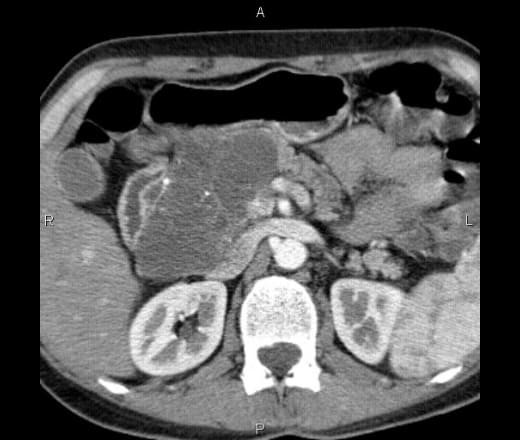

Компьютерная томография — высокоинформативное исследование, позволяющее обнаружить патологические изменения внутри организма без инвазивного проникновения: диагностические манипуляции не нарушают целостность тканей, как при лапароскопии. Множество срезов в поперечной проекции обрабатывает специальная программа. При помощи реконструкции получают изображения в других плоскостях и объемную модель зоны интереса.

КТ внутренних органов показывает:

На снимках видны:

внутренние органы: паренхиматозные — печень, почки, селезенка, простата — и полые — трахея, пищевод, кишечник, мочеточники, мочевой пузырь;

Органы брюшной полости, ретроперитонеального пространства. КТ живота является точным методом для диагностики абдоминальных патологий:

опухолей (КТ показывает стадию и распространенность рака, ответ на лечение).

КТ брюшной полости является современным и точным рентгенологическим способом диагностики органов, расположенных в брюшной области. Во время обследования происходит томографическое, то есть, послойное сканирование исследуемой зоны. Современные мультспиральные томографы способны за один оборот сканера делать от 32 до 640 срезов, а мощный компьютер может создать трехмерные реконструкции всех анатомических структур области живота. Данные КТ снимков позволяют выявить воспалительные процессы и опухолевые изменения в костных и мягкотканных структурах.

Процедура компьютерной томографии органов брюшной полости проходит по двум базовым протоколам — нативная и контрастная. МСКТ с контрастным усилением предполагает использование контрастных препаратов на базе йода, которые улучшает тканевую контрастность на томограммах и позволяет определить новообразования на этапе развития. Кроме того, существует агиографическая форма обследования (КТ брюшной аорты и сосудов) области живота, когда врачи прицельно оценивают сосудистую систему брюшной полости.

Компьютерная томография, в отличие от базовой УЗИ и рентгена, максимально развернуто оценивает структуру ОБП. Такая диагностическая точность достигается за счет возможности делать множественные снимки с различных ракурсов. Принцип работы компьютерного томографа основывается на способности рентгеновских лучей проходить с разной скоростью через ткани различной плотности. Во время сканирования датчик рентгеновского излучателя движется по периметру кольца Гентри вокруг тела пациента. Пучки рентгеновских лучей проходят под разными ракурсами через ткани брюшной области, их остаточная мощность фиксируется приемником на другой стороне кольца. На базе этих данных компьютер томографа строит трёхмерные реконструкции.

Что показывает МСКТ органов брюшной полости

КТ обследование брюшной полости и забрюшинного пространства помогает выявить ряд заболеваний:

КТ брюшной полости с контрастом способствует наиболее четкому отображению тканей и часто используется при онкопоиске. Контрастирование позволяет установить опухолевые очаги и степень их распространения на соседние участки. Контраст распространяется в крови и как бы “подкрашивает” ткани. Обязательного контрастного усиление потребует КТ ангиография сосудов брюшной полости. Без контрастирования сосудистая сеть на компьютерной томографии не видна.